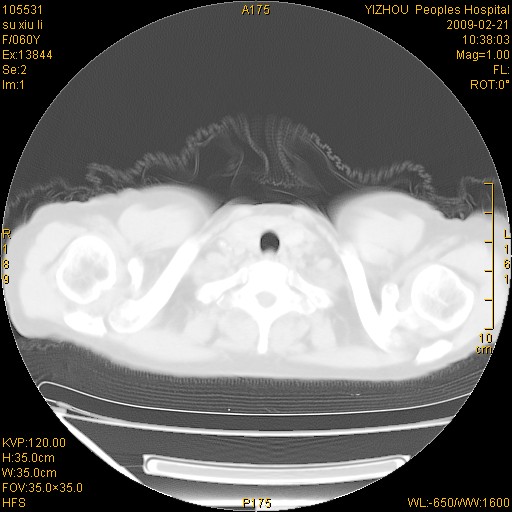

标题: CT18259:两肺间质纤维化? [打印本页]

标题: CT18259:两肺间质纤维化?

女,60岁,反复咳嗽1月。

两肺支扩,以肺为著合并双肺较广范纤维化病变。建议除外结核等病变。

间质性肺炎

符合间质感染,部分纤维化表现

特发性间质纤维化

特发性间质纤维化伴支扩!